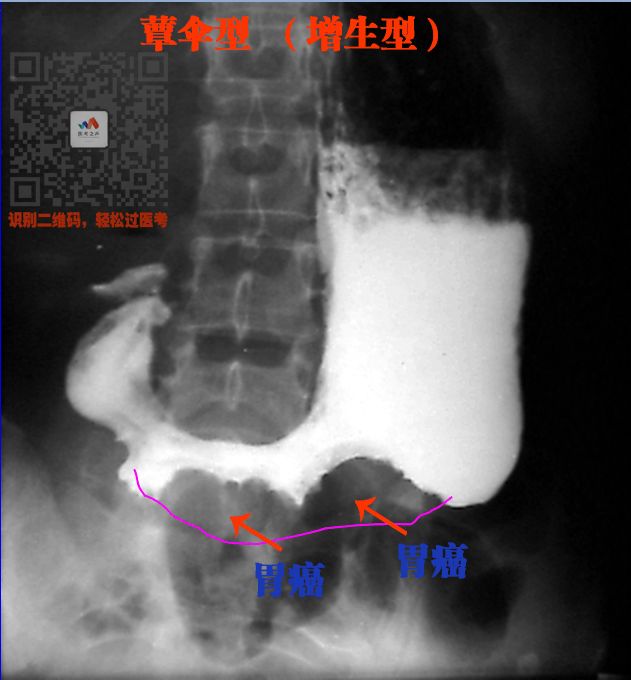

④ 胃癌

胃癌有不同的生长方式

所以表现也不一致

增生型

胃腔里面突出一个肿瘤

这块肿瘤不能被钡剂填充

所以表现充盈缺损(胃好像掉了一块)

看图

胃部就考两2个病:

墙(轮廓)内犯人(坏),墙外好人

向轮廓外突出一个小鸡鸡,选胃溃疡

胃里面钡剂少了(充盈缺损,狭窄)

就选胃癌